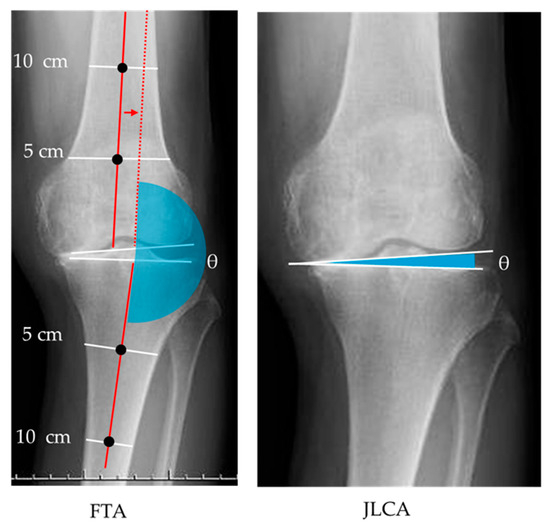

Effects of Weight-Bearing-Induced Changes in Tibial Inclination Angle on Varus Thrust During Gait in Female Patients with Knee Osteoarthritis

by

Ryosuke Karashima, Shintaro Kishimoto, Takuya Ibara, Kiyotaka Hada, Tatsuo Motoyama, Masayuki Kawashima, Yusuke Murofushi and Hiroshi Katoh

Biomechanics 2025, 5(4), 98; https://doi.org/10.3390/biomechanics5040098 - 1 Dec 2025

Background: The relationship between varus thrust (VT) during gait and static limb alignment on radiography in knee osteoarthritis (OA) remains unclear. Therefore, the present study investigated the association between the tibial inclination angle (TA), which was noninvasively measured from the body surface, and

Background: The relationship between varus thrust (VT) during gait and static limb alignment on radiography in knee osteoarthritis (OA) remains unclear. Therefore, the present study investigated the association between the tibial inclination angle (TA), which was noninvasively measured from the body surface, and radiographic parameters. In Addition, this study analyzed how TA changes under different loading conditions (ΔTA) relate to VT acceleration (VTA) during early stance using an inertial measurement unit (IMU) sensor. Methods: Nineteen female patients (mean age: 63.5 ± 8.6 years) with knee OA or medial meniscus injury were included. The TA was defined as the angle between the tibial mechanical axis and a vertical line from the floor, which was measured in standardized standing and supine positions. The ΔTA was calculated as the difference between these positions. To assess lower limb alignment, the femorotibial angle (FTA) and joint line convergence angle (JLCA) were measured. The VTA was measured using IMU sensors on the thigh and tibia, and the differences between lateral and medial VTA were defined as femoral and tibial ΔVTA, respectively. Spearman’s correlation coefficient and linear regression were used for analysis. Results: The standing TA was significantly correlated with the FTA (ρ = 0.47, p = 0.04) and JLCA (ρ = 0.80, p < 0.01). The ΔTA was significantly associated with femoral ΔVTA (β = 0.70, p < 0.01) and tibial ΔVTA (β = 0.67, p < 0.01). Conclusions: Surface-measured TA reflects radiographic alignment. The ΔTA also captures dynamic instability not explained by static measures, suggesting its potential utility as an assessment indicator, although further validation is warranted.